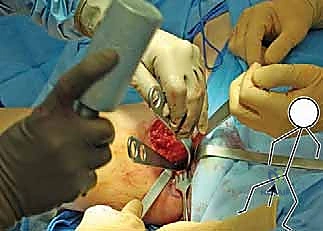

تُجرى العملية تحت التخدير العام. يُوضع المريض على طاولة العمليات بوضعية تسمح بالوصول الكامل إلى منطقة الحوض، مع استخدام المراقبة العصبية المستمرة لضمان سلامة الأعصاب الكبرى في الساق (مثل العصب الوركي والعصب الفخذي).

2. الشقوق الجراحية (Incisions)

يُجري الدكتور هطيف شقوقاً استراتيجية مصممة لتقليل الضرر العضلي وترك ندبات تجميلية صغيرة قدر الإمكان. يتم الوصول إلى العظام الثلاثة بعناية فائقة وتجنيب الأوعية الدموية الحساسة.

3. مرحلة القطع العظمي (The Three Osteotomies)

هنا تكمن عبقرية الإجراء. يتم استخدام مناشير جراحية دقيقة لعمل قطوع في: